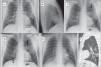

Our recent experience reporting DTS in patients with suspected COVID-19 suggests that this technique is more useful when pulmonary opacities are subtle and therefore more difficult to identify by X-ray. It also facilitates the detection of multiple peripheral opacities, confirming bilateral involvement in many cases; characteristics that, as already mentioned, are associated with COVID-19. In this respect, DTS is more specific than chest X-ray in this disease. By providing a series of coronal slices, pulmonary opacities that may be faint or posterior can be more accurately located than with lateral X-ray (Fig. 1) (annex, Supplementary Figs. 1 and 2). It is not a matter of opinion. It is a conclusion generated by what was experienced with these patients. The main limitation of this technique is the respiration-mediated artifacts caused by the difficulty of some patients in holding their breath during the examination.

Bilateral COVID-19 pneumonia. A 52-year-old man, family doctor by profession, presented with a 10-day history of cough and myalgia. Dyspnea and fever on examination. Laboratory tests: normal white cell count, ferritin 545.7 ng/mL (>322), and erythrocyte sedimentation rate 53 m/n (0–20). PCR positive for SARS-CoV-2. A— Posterior-anterior chest X-ray: slight opacity in the periphery of the left hemitorax, middle field. B—Lateral chest X-ray with no obvious findings. C—DTS: Image no. 8 (anterior). Extensive opacity in anterior region of left hemitorax (arrows). D—DTS: Image no. 14 (central). Bilateral pulmonary opacities, in the left suprahilar region (arrow) and right lower lobe (arrow). E—DTS: Image no. 36 (posterior). Oval opacity in retro-cardiac region (arrow). F—Non-contrast chest CT scan, sagittal reconstruction. Oval opacity in the periphery of the left lower lobe (arrow).